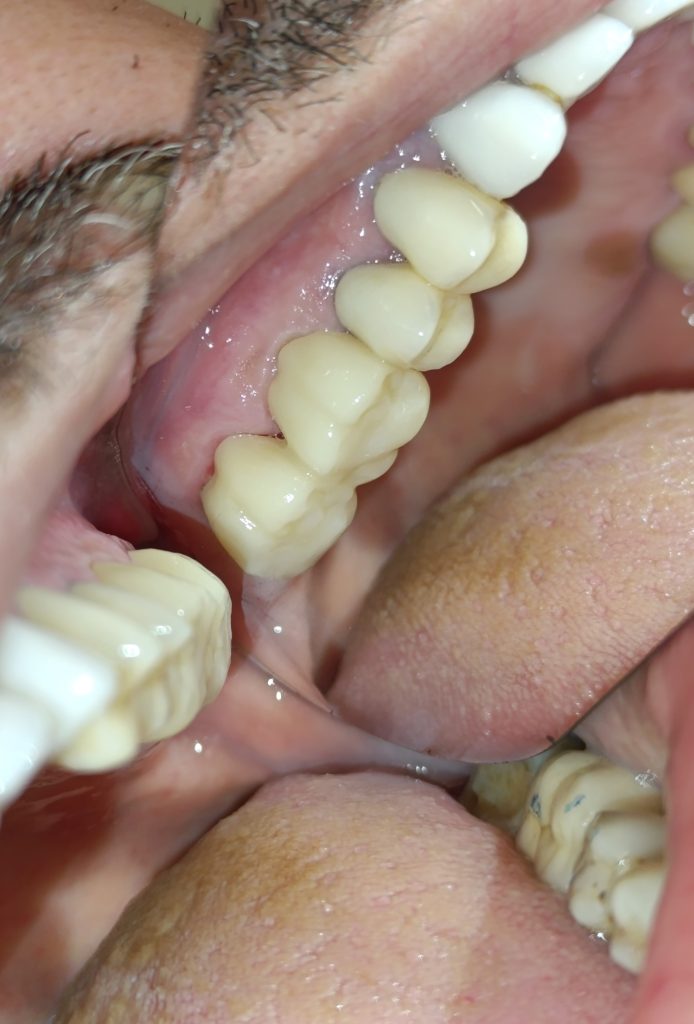

Περιστατικό – Ολοκεραμικές θήκες ζιρκονίου στην αριστερή πλευρά της άνω γνάθου

Ο ασθενής είχε δύο παλιές μεταλλοκεραμικές θήκες, οι οποίες με την πάροδο του χρόνου τερηδονίστηκαν, φθάρθηκαν (είχε φθαρεί η κεραμική κάλυψη των θηκών) και έπρεπε να αντικατασταθούν με νέες (απουσιάζει η φωτογραφία της αρχικής εικόνας). Εφόσον αφαιρέθηκαν οι παλιές θήκες πραγματοποιήθηκαν όλες οι απαραίτητες οδοντιατρικές εργασίες (απονεύρωσεις δοντιών, ανασύστασεις / σφραγίσματα δοντιών) όπου ήταν απαραίτητο, προκειμένου να κατασκευαστούν νέες ολοκεραμικές θήκες ζιρκονίου.

Στο μεσοδιάστημα που μεσολάβησε ώστε ο οδοντοτεχνίτης να κατασκευάσει τις νέες θήκες δοντιών, τα τροχισμένα δόντια ήταν προστατευμένα με προσωρινές στεφάνες.

Η νέα γέφυρα είχε ένα πολύ καλό αισθητικό και λειτουργικό αποτέλεσμα.

Τα δόντια μετά τις απαραίτητες απονευρώσεις και τις ανασυστάσεις

ΤΕΛΙΚΗ ΕΙΚΟΝΑ